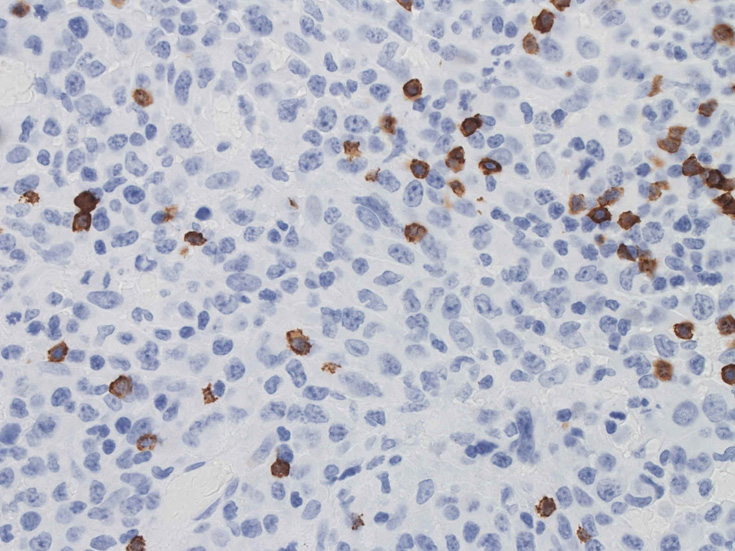

免疫染色の所見

CD30はほぼ全ての腫瘍細胞に陽性となる。膜とゴルジ装置が染まり, 図のように細胞質内に斑点状の染まりが認められます。この症例では多くの腫瘍細胞がCD5陽性となり、CD30と同じ染色パターンを呈しました。